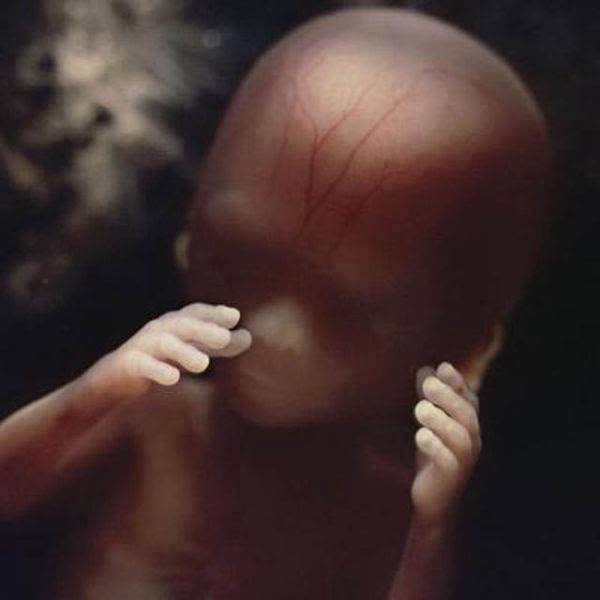

Nilsson ha poi ripreso le prime fasi di sviluppo del cervello, del cuore (che avviene verso il ventiquattresimo giorno), e, alla quinta settimana, il crearsi delle fessure che diventeranno gli occhi, la bocca e le orecchie. Dopo 40 giorni viene documentato il formarsi della placenta, che permette all’embrione di ricevere il nutrimento necessario.

Sarà dopo 8 settimane che il feto comincerà ad assumere una forma umana riconoscibile. Pian piano iniziano poi a formarsi gli occhi, le palpebre, i vasi sanguigni e la cartilagine. Già dopo 16 settimane, il bambino inizierà ad esplorare ciò che lo circonda.